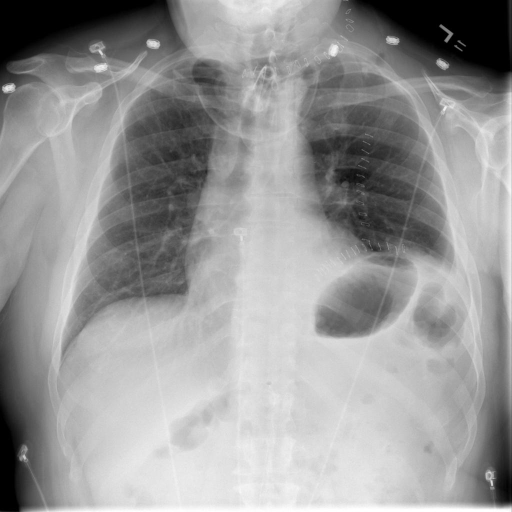

In Fig. 4, we show qualitative examples of the calculation of the cardio-thoracic-ratio for patients presenting cardiomegaly and not presenting cardiomegaly. For the case of the pathology, we see that the border of the heart is expanded, leading to a CTR above 0.7, whereas, for the absence case, the CTR is 0.4255.

When conducting a t-test, we get a value of 139.71 (p-value 0.0001) indicating a strong difference in CTR between positive and negative patients for cardiomegaly. We show this property in the violin plots on the left of Fig. 4, highlighting the CTR distributions for sex, age group, and pathology. Typically, the CTR for the presence and absence of cardiomegaly has noticeable shifts, with both respective means increasing with age. This average increase in CTR, however, becomes less in the age group of , with the disparity in mean CTR between cardiomegaly and no cardiomegaly reducing the older a patient gets. This result, in turn, lessens the insight of CTR with age. We observe this property for male and female patients. On the right of Fig. 4, we show the ROC-Curve for pathology classification based on the CTR score. We see a difference in the diagnostic performance of the CTR for female and male patients with an AuROC of 0.73 and 0.75.

In Fig. 4, we show qualitative examples of the calculation of the SCD for patients for the presence and absence of scoliosis. We can see that the vertebrae segmentation presents a noticeable curvature for the scoliosis case, leading to an SCD above 19, while for the patient with a healthy spine, the SCD is 1.125.

When conducting a t-test, we get a value of 35.30 (p-value 0.0001), indicating a statistically significant difference in SCD between positive and negative patients for scoliosis. On the left of Fig. 4, we show the distributions of the SCD in the form of violin plots for sex, age group, and pathology. Similarly to the CTR, SCD increases with age for the presence and absence of scoliosis. The results show that the older the patient gets, the less the disparity in mean SCD between scoliosis and no scoliosis becomes, indicating that the SCD becomes slightly less insightful the older the patient is. However, different from the CTR, the standard deviation of the SCD is considerably higher, and there is a relatively larger difference in means, leading to a higher predictive value for the identification of scoliosis.